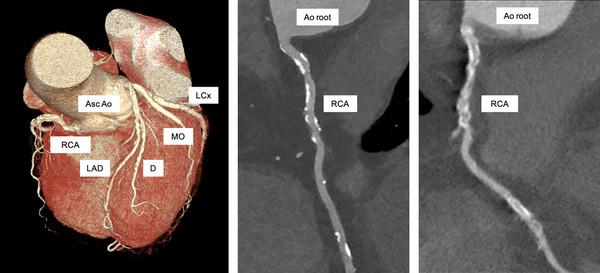

Advancements in coronary computed tomography angiography (CCTA) facilitated the transition from traditional histological approaches to comprehensive plaque burden assessment. Recent updates in the European Society of Cardiology (ESC) guidelines emphasize CCTA's role in managing chronic coronary syndrome by enabling detailed monitoring of atherosclerotic plaque progression. Limitations of conventional CCTA, such as spatial resolution challenges in accurately characterizing plaque components like thin-cap fibroatheromas and necrotic lipid-rich cores, are addressed with photon-counting detector CT (PCD-CT) technology. PCD-CT offers enhanced spatial resolution and spectral imaging, improving the detection and characterization of high-risk plaque features while reducing artifacts. The integration of artificial intelligence (AI) in plaque analysis enhances diagnostic accuracy through automated plaque characterization and radiomics. These technological advancements support a comprehensive approach to plaque assessment, incorporating hemodynamic evaluations, morphological metrics, and AI-driven analysis, thereby enabling personalized patient care and improved prediction of acute clinical events.

冠状动脉计算机断层扫描血管造影(CCTA)的进展推动了从传统组织学方法向全面斑块负荷评估的转变。欧洲心脏病学会(ESC)指南的最新更新强调了CCTA在管理慢性冠状动脉综合征中的作用,它能够对动脉粥样硬化斑块进展进行详细监测。传统CCTA存在局限性,比如在准确识别薄帽纤维粥样瘤和富含坏死脂质核心等斑块成分时面临空间分辨率挑战,而光子计数探测器CT(PCD-CT)技术解决了这些问题。PCD-CT提供了更高的空间分辨率和光谱成像,在减少伪影的同时,提高了对高危斑块特征的检测和识别能力。人工智能(AI)在斑块分析中的整合通过自动斑块特征描述和放射组学提高了诊断准确性。这些技术进步支持了一种全面的斑块评估方法,包括血流动力学评估、形态学指标和AI驱动的分析,从而实现个性化患者护理并改善急性临床事件的预测。